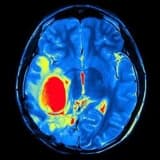

DİAQNOZ

Əgər miqren baş ağrınız varsa və ya ailənizdə miqren tarixi varsa, həkiminiz fiziki müayinə, tibbi tarix və simptomlar əsasında diaqnoz qoyacaq. Əgər qeyri-adi və ya şiddətli miqren tipli baş ağrılarınız varsa və ya baş ağrılarınız və nevroloji simptomlarınız pisləşirsə, ağrının digər səbəblərini istisna etmək üçün müəyyən testlər tövsiyə oluna bilər. Bunlar qan testləri, beyin görüntüləmə tədqiqatları (homputerləşdirilmiş tomoqrafiya və ya maqnit rezonans görüntüləmə), göz müayinəsi və digər şöbələrlə məsləhətləşmələr ola bilər. Həkiminiz sizdən miqren gündəliyi tutmağınızı istəyə bilər.Migren baş ağrısının nə vaxt başladığı, nə qədər sürdüyü, ağrının miqdarı, əvvəllər olan simptomlar, ondan sonra və ya zamanı olan əlamətlər və ağrının necə keçdiyi qeyd edilməlidir. Həmçinin, fişdən 24 saat əvvəl tetikleyicileriniz, dərmanlarınız və stress səviyyəniz qeyd edilməlidir. Bu məlumat sizin müalicə planınızı və müalicəyə cavabınızı qiymətləndirmək üçün vacibdir.